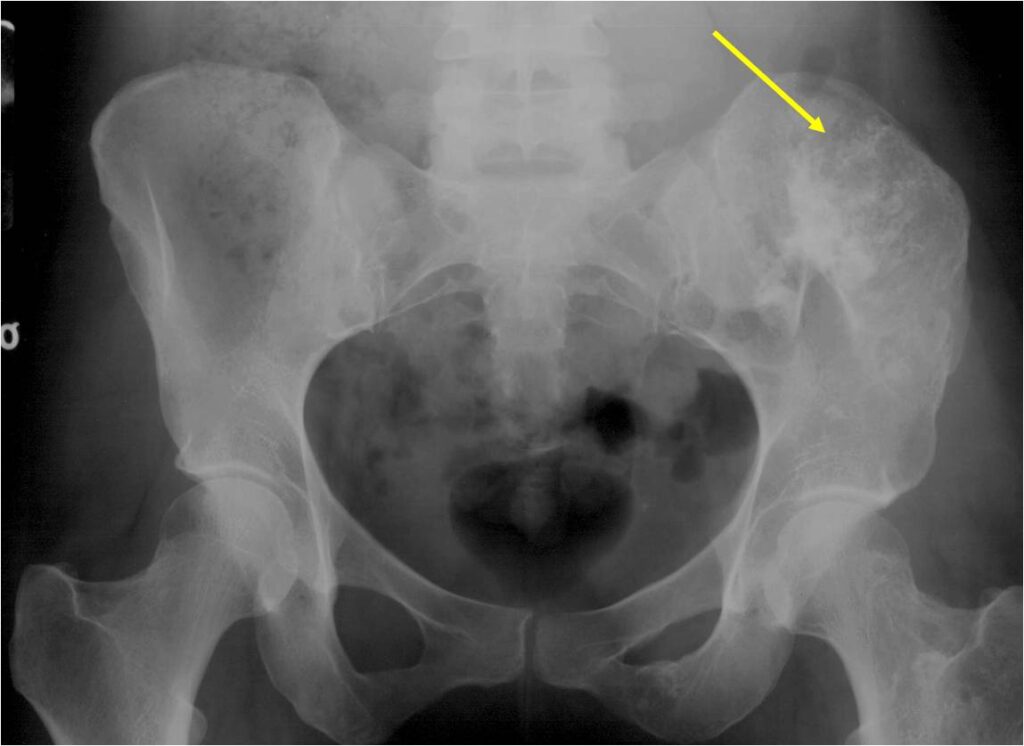

- Enchondromas of the pelvis, vertebrae and ribs are uncommon

- Almost all hyaline cartilage tumors of the pelvis are considered malignant based on anatomic location no matter what the pathology shows. These tumors will ultimately grow locally and have the potential to dedifferentiate or change into a higher grade chondrosarcoma.

- The most common sites to undergo malignant change are the scapula, rib cage and pelvis